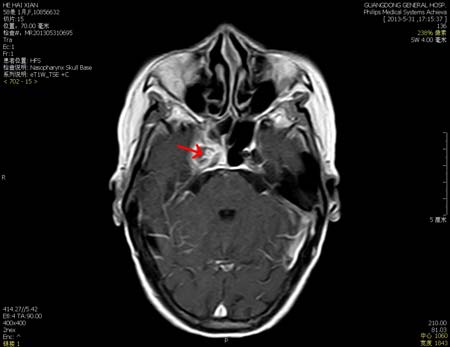

箭头所示为右侧颅底病灶,累及右侧蝶窦、海绵窦,增强后有明显环形强化,右颈内动脉被包绕并狭窄

患者入院后,经过鼻咽和颅底增强MR检查,结果显示:右侧颅底海绵窦岩尖存在异常信号影,提示该区域有病变,邱主任初步确定为慢性炎症性病变,右侧蝶窦和乳突有炎性病灶。经科组讨论,决定为该患者施行内窥镜下鼻颅底手术,主刀是邱前辉主任。手术经右侧鼻腔进路,开放后组筛窦及蝶窦,发现蝶窦内较多褐色的真菌团,蝶窦腔粘膜肿胀,质地脆,证实了邱主任术前的诊断。炎性坏死组织已侵蚀右侧颈内动脉骨管,引致右侧颈内动脉蝶窦段骨质缺损、动脉裸露于蝶窦腔,并且炎症还从颈内动脉后上进入海绵窦。